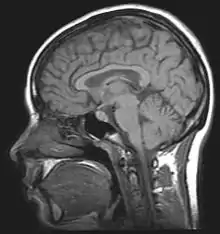

Alcohol-related brain damage[1] alters both the structure and function of the brain as a result of the direct neurotoxic effects of alcohol intoxication or acute alcohol withdrawal. Increased alcohol intake is associated with damage to brain regions including the frontal lobe,[2] limbic system, and cerebellum,[3] with widespread cerebral atrophy, or brain shrinkage caused by neuron degeneration. This damage can be seen on neuroimaging scans.[4]

Neuroimaging is used to study the effect that alcohol has on the brain. The two main imaging methods are hemodynamic and electromagnetic. These techniques have allowed for the study of the functional, biochemical, and anatomical changes of the brain due to prolonged alcohol abuse.[2] Neuroimaging provides valuable information in determining the risk an individual has for developing alcohol dependence and the efficacy of potential treatment.[2][17]

Magnetic resonance imaging (MRI) and functional magnetic resonance imaging (fMRI) are other commonly used tenichiques. These methods are noninvasive, and have no radioactive risk involved. The fMRI method records the metabolic changes in a particular brain structure or region during a mental task. To detect damage to white matter, the standard MRI is not sufficient. An MRI derivative technique known as diffusion tensor imaging (DTI) is used to determine the orientation and integrity of specific nerve pathways, allowing the detection of damage.[2] When imaging those with alcoholism, the DTI results show that heavy drinking disrupts the microstructure of nerve fibers.[2] Another MRI derivative technique, magnetic resonance spectroscopy imaging (MRSI), can provide further information about the brain's neurochemistry and can detect the distribution of certain metabolites, neurotransmitters, and alcohol.